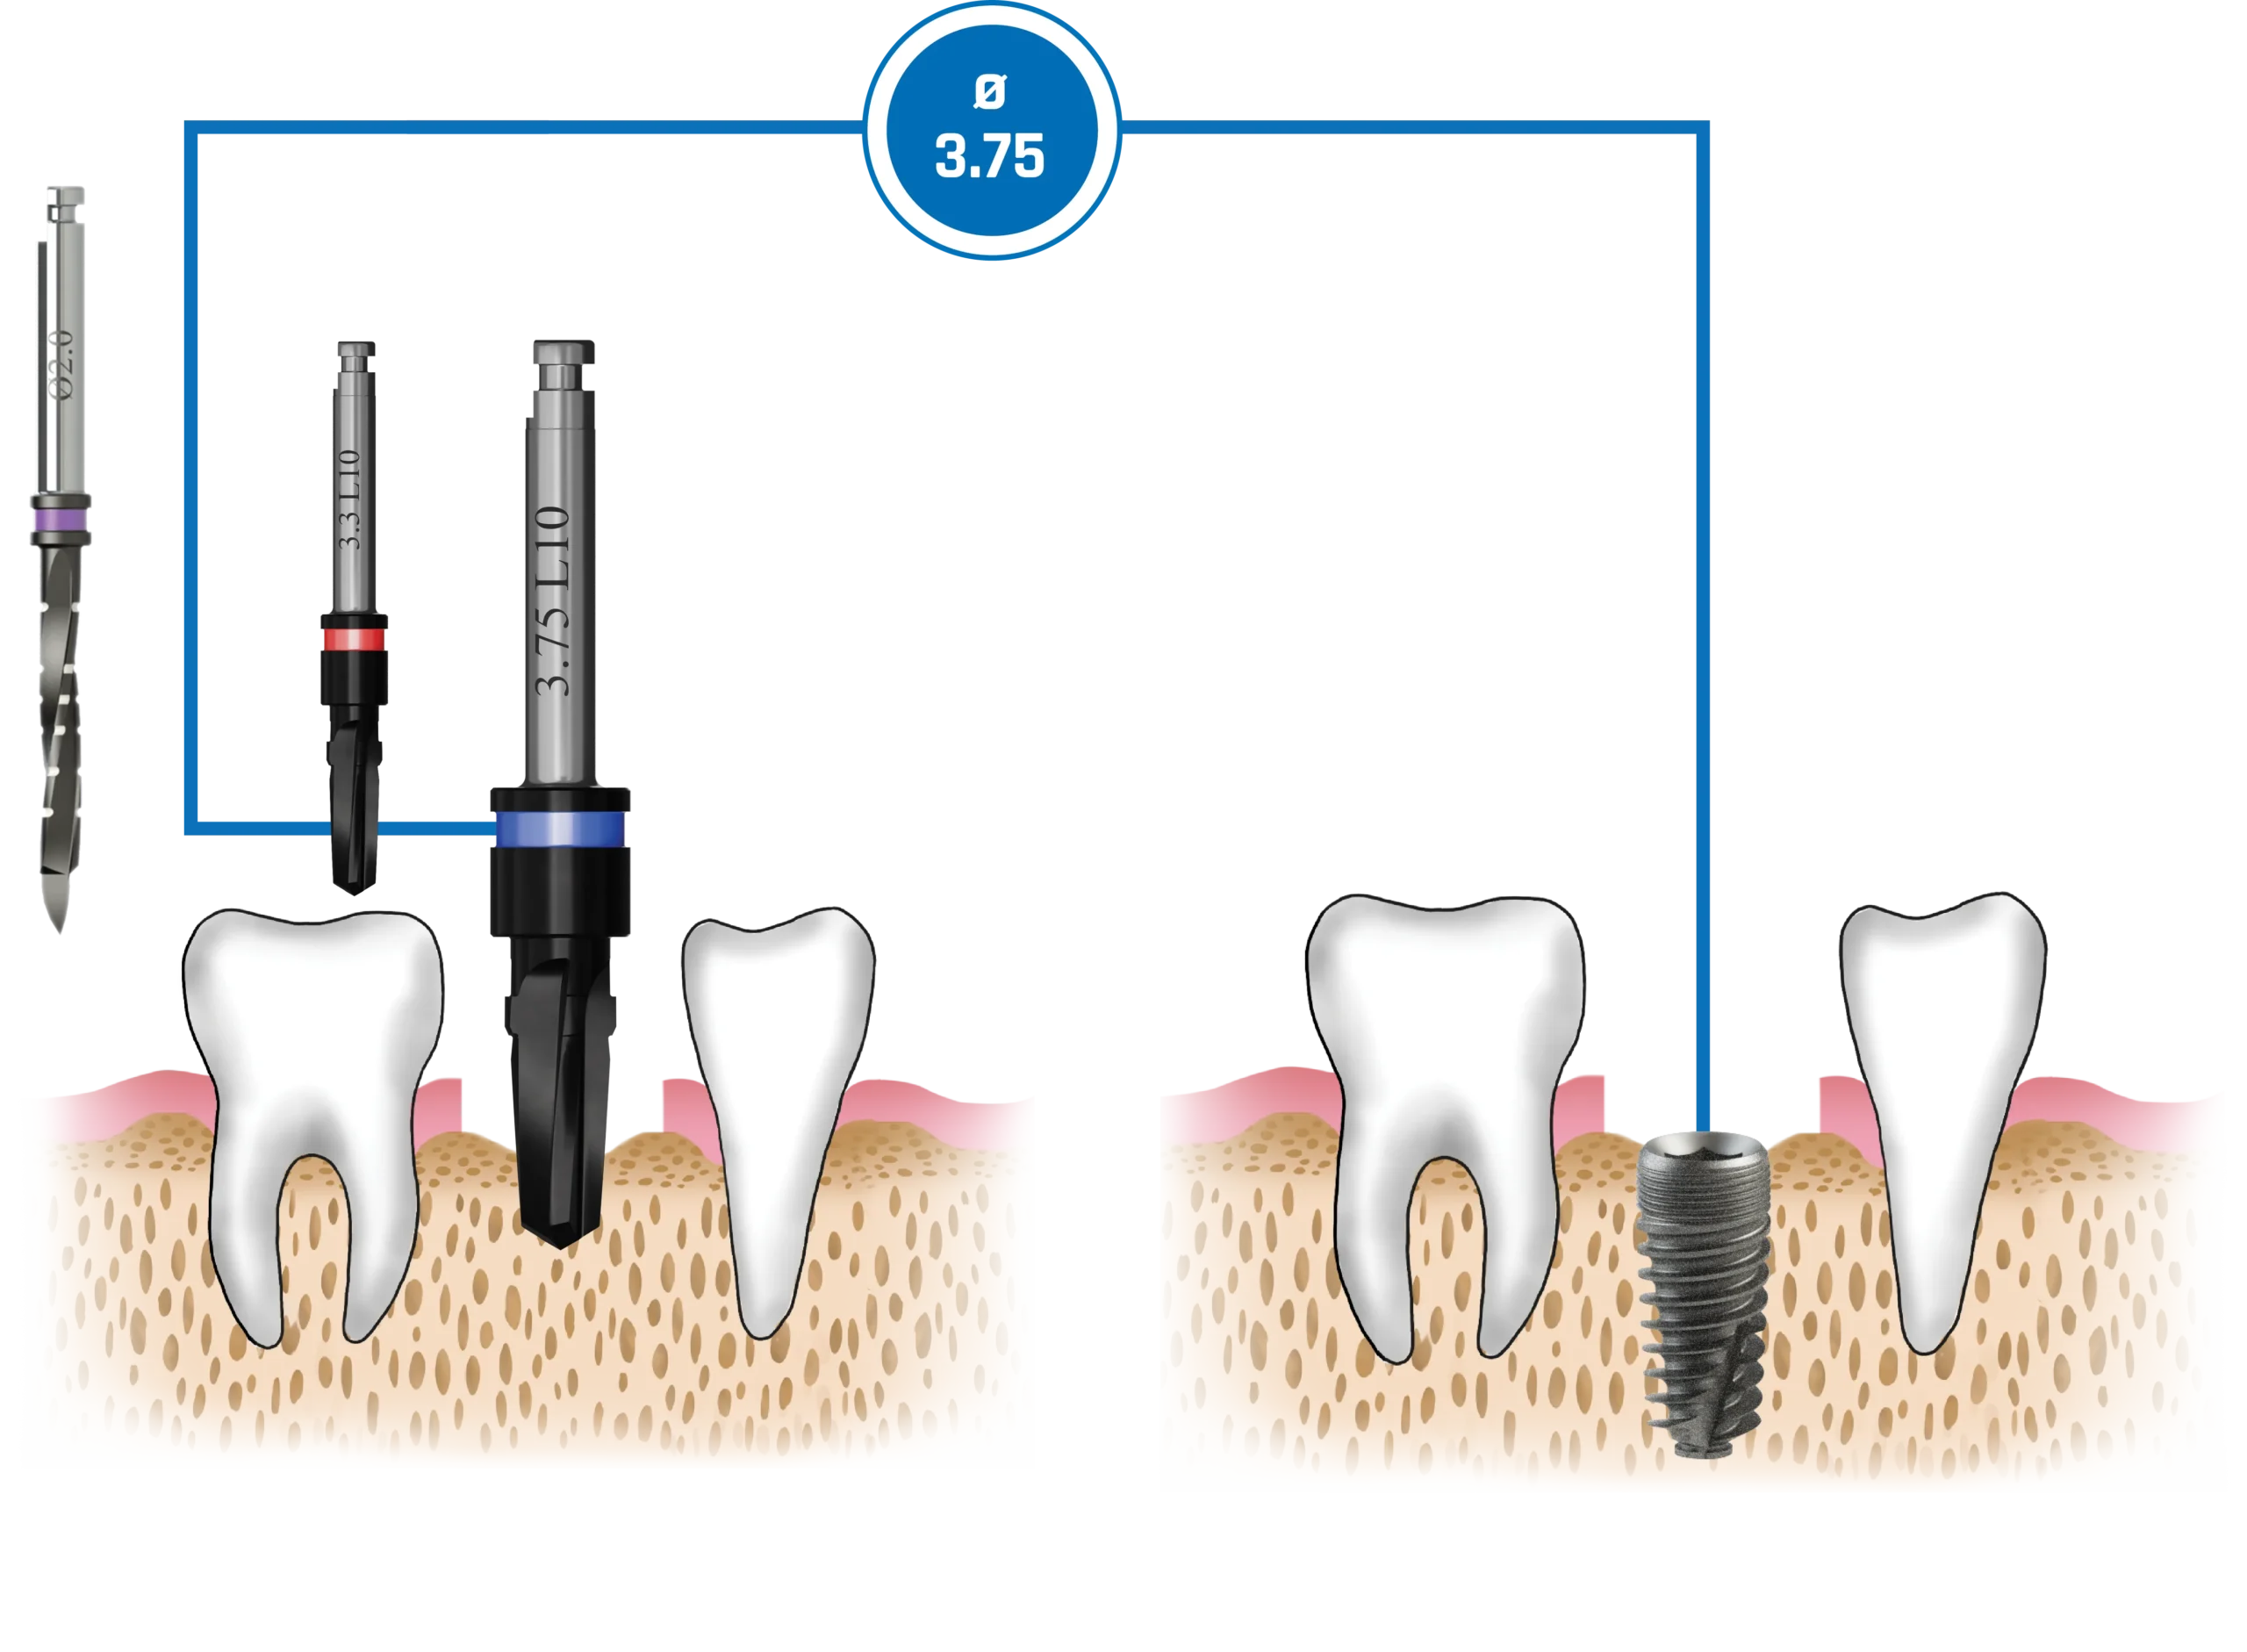

Quy trình mũi khoan

Nên sử dụng mũi khoan mồi 2.0 mm cho tất cả các đường kính implant. Các implant có đường kính 3.0 mm và 3.3 mm (Dòng Hẹp – Narrow Line) cùng với implant đường kính 3.75 mm (Dòng Tiêu Chuẩn – Standard Platform) nên được đặt ngang mức đỉnh xương. Các implant đường kính 4.2 mm, 5.0 mm và 6.0 mm (Dòng Tiêu Chuẩn – Standard Platform) có thể được đặt dưới mức đỉnh xương